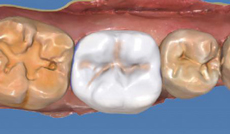

型態一鍵產生

透過 Biogeneric 生物仿真技術

軟體將依照鄰牙特徵自動建議出符合每位患者的修復體

包括其修復體型態、咬合力度及鄰接力度…等

大幅縮短使用者的設計時間

及醫師的試戴時間

發育溝紋模擬

透過 Biogeneric Variation 工具

使用者可輕易創造如同自然牙般特殊的發育紋路及線條

,使修復體型態更具豐富的立體感及細膩度